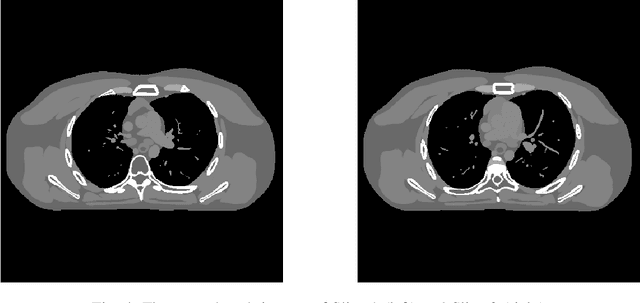

Abstract:Obtaining accurate and reliable images from low-dose computed tomography (CT) is challenging. Regression convolutional neural network (CNN) models that are learned from training data are increasingly gaining attention in low-dose CT reconstruction. This paper modifies the architecture of an iterative regression CNN, BCD-Net, for fast, stable, and accurate low-dose CT reconstruction, and presents the convergence property of the modified BCD-Net. Numerical results with phantom data show that applying faster numerical solvers to model-based image reconstruction (MBIR) modules of BCD-Net leads to faster and more accurate BCD-Net; BCD-Net significantly improves the reconstruction accuracy, compared to the state-of-the-art MBIR method using learned transforms; BCD-Net achieves better image quality, compared to a state-of-the-art iterative NN architecture, ADMM-Net. Numerical results with clinical data show that BCD-Net generalizes significantly better than a state-of-the-art deep (non-iterative) regression NN, FBPConvNet, that lacks MBIR modules.